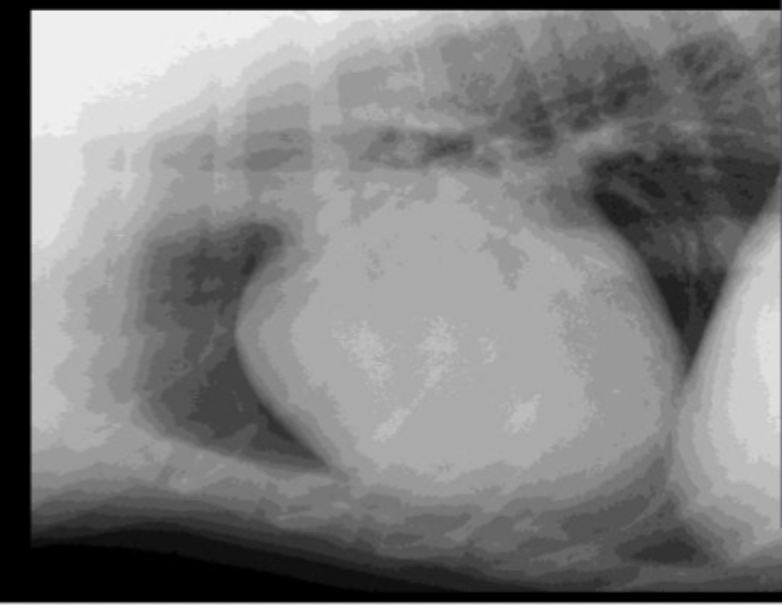

What can be seen in these cat radiographs?

Nothing, these radiographs are normal